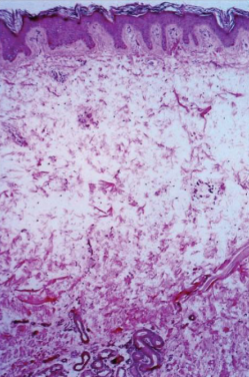

Infiltrative Dermopathy

Skin: separation of collagen fibers by mucin in reticular dermis